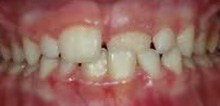

Health and Success − Aesthetics and Function